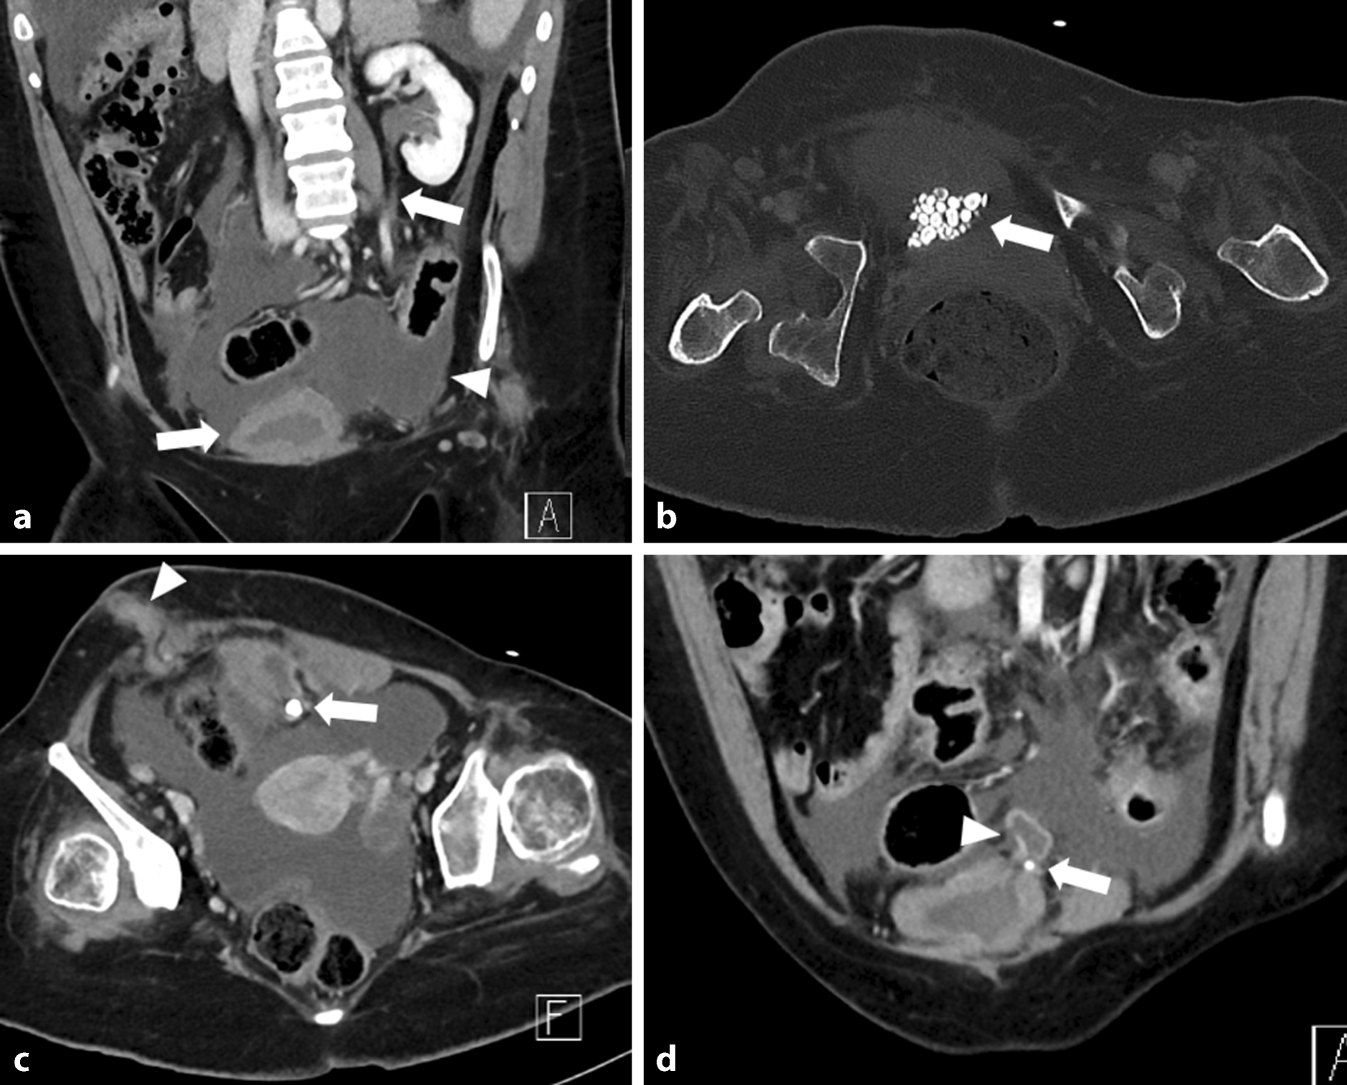

In der durchgeführten CT (Abb. 1) zeigte sich bei ausgeprägtem Aszites eine deutliche Kontrastmittelaufnahme des peritonealen Blattes als Ausdruck einer Peritonitis. Ferner ließen sich multiple Konkremente innerhalb der wandverdickten Harnblase im Sinne einer chronischen Inflammation bzw. bei bekannter neurogener Dysfunktion feststellen. Des Weiteren zeigte sich eine gesteigerte Kontrastmittelaufnahme des Ureters und des Nierenbeckenkelchsystems (NBKS) im Sinne einer diffusen Entzündung. Links kranial war am Dach der Blase eine divertikelartige Aussackung mit Konkrementeinschluss abzugrenzen. Die Wand des Divertikels war zart, kurzstreckig war die Kontinuität der Wand nicht abgrenzbar. Im Verlauf der Ausleitung im rechten Unterbauch zeigte sich ebenfalls eine deutliche Entzündungsreaktion. Zur Darstellung der Abflussverhältnisse wurde eine urographische Phase angefertigt (Abb. 2).

Abb. 1

Computertomographie (CT) des Abdomens mit Kontrastmittel in portalvenöser Phase in koronarer (ad) und axialer (bc) Rekonstruktion (acd Weichteilfenster, b Knochenfenster). a Es zeigt sich im Unterbauch die zirkulär wandverdickte Harnblase und der kontrastmittelaufnehmende Ureter links (Pfeile). Zudem ist reichlich Flüssigkeit im Unterbauch und ein verdicktes, kontrastmittelaufnehmendes Peritoneum zu erkennen (Pfeilspitze). b Innerhalb der Blase finden sich multiple röntgendichte Konkremente (Pfeil). c Die Blase zeigt ein nach links kranial gerichtetes Divertikel mit einem darin befindlichen Konkrement (Pfeil). Die Ausleitung des Mitrofanoff-Stoma im rechten Unterbauch ist verdickt und nimmt Kontrastmittel auf (Pfeilspitze). d Abgebildet ist erneut die wandverdickte Blase mit dem nach links kranial gerichteten Divertikel und dem teilweise erfassten Konkrement (Pfeil). Die Wand des Divertikels zeigt eine Konturunterbrechung (Pfeilspitze)